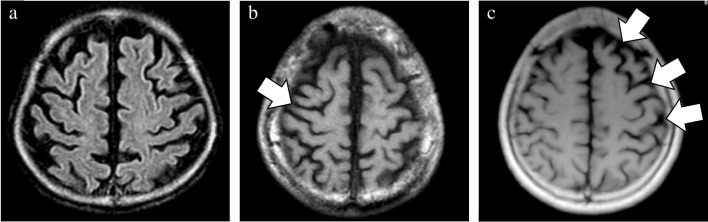

In addition to the well-established GCA and MTA scales, newly devised rating scales were utilized to evaluate the presence of midbrain atrophy and asymmetric atrophy. The degree of midbrain atrophy was assessed using a three-point scale (0 = normal, 1 = mild, and 2 = severe) primarily on sagittal T1WIs (Fig. 1). Mild midbrain atrophy indicated a slight reduction in the anteroposterior and/or superoinferior diameters. By contrast, a definitive decrease in these diameters was classified as severe midbrain atrophy. The degree of asymmetry in the frontal, temporal, parietal, and occipital lobes, along with the cerebral peduncle, was assessed using a three-point scale (0 = normal, 1 = mild, and 2 = severe) on axial T1WIs (Fig. 2). Severe asymmetry indicated the definite dilation of the sulcus and/or narrowing of the gyrus between the two hemispheres. Conversely, a case with unremarkable asymmetry was rated as mild.